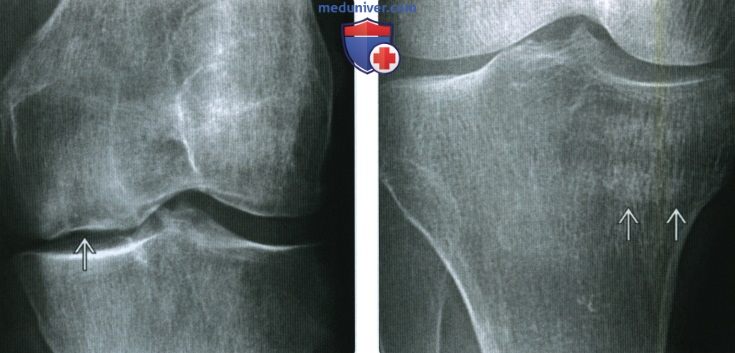

Медицинские снимки: рентген коленного сустава при остеопорозе